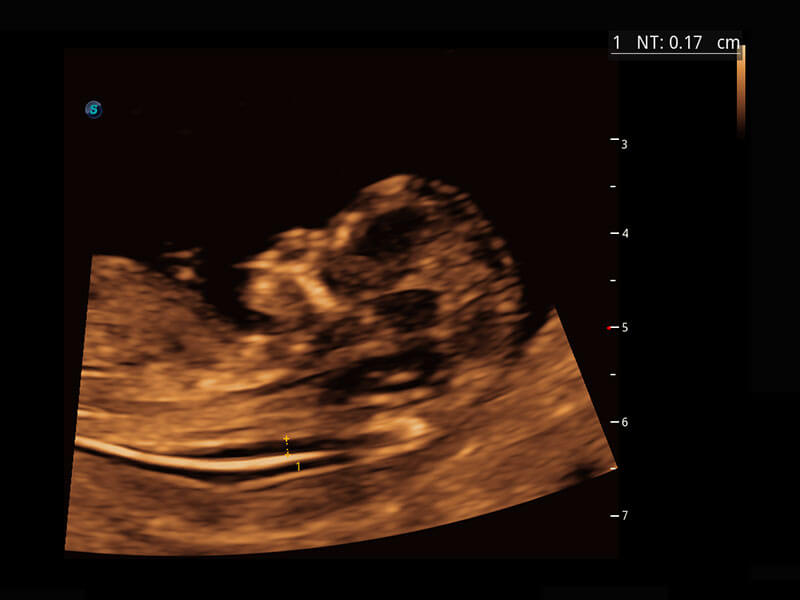

P60在胎兒早孕期超聲篩查中為您帶來優(yōu)異的圖像質(zhì)量。

早孕-胎心

高分辨率容積成像-早孕胎兒

胎兒體循環(huán)

光影成像-孕囊